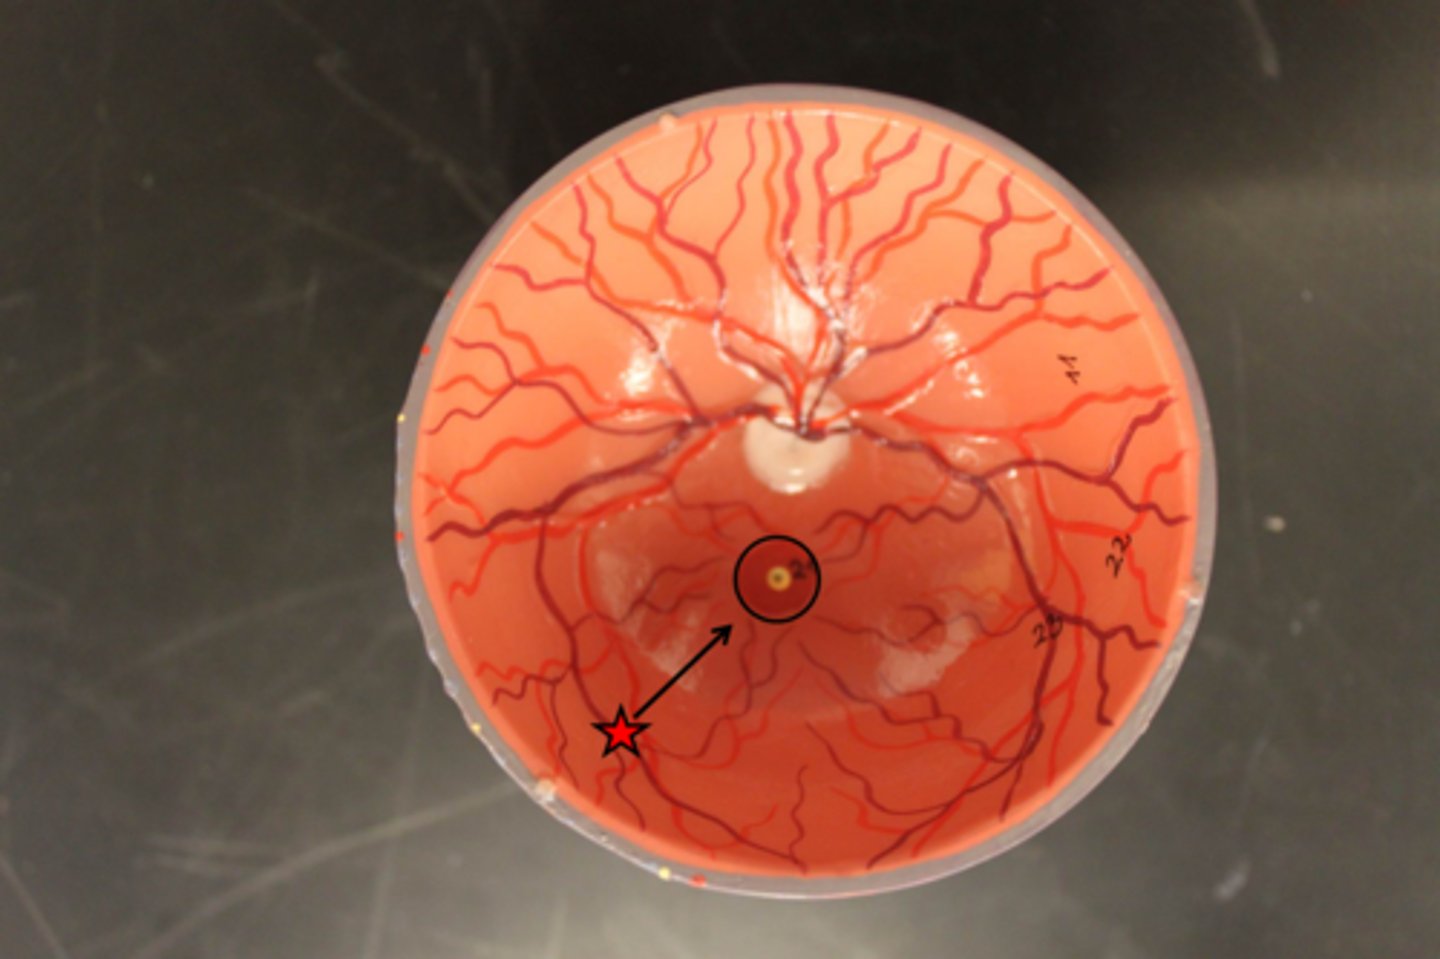

An increased number of drusen in the macular area are noted on ophthalmoscopic examination. What action should follow?

Ask the patient to self-test using the Amsler grid.

(Unexpected Findings): Small discrete spots that are slightly more yellow than the retina. With time the spots enlarge.

Drusen bodies; commonly they are a consequence of thee aging process